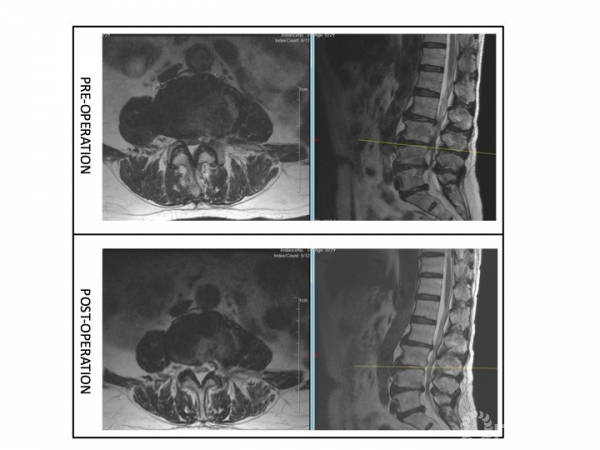

查体:视触动量等检查均无明显阳性体征,病理征、四肢腱反射等神经查体均正常。核磁提示:L3/4、L4/5椎管狭窄,L3/4纤维环HIZ,L4/5左侧隐窝狭窄,L5/S1纤维环HIZ。腰椎稳定性可。(图7)

图7

图8

解决方案(图9):

① 腰椎间盘造影L3/4:注射2.5ml造影剂后,造影剂沿HIZ向椎管内渗漏,但未诱发下腰痛或放射痛;

② 腰椎间盘造影L4/5:注射2.5ml造影剂后,造影剂在间盘内分层,诱发出下腰痛,复制出轻度的左下肢放射痛;

③ L5出口根造影:穿刺针刺激出口根,复制出明显相同部位的放射痛,局部注射造影剂0.5ml[2],沿出口根走行显影,局部注射局麻药+类固醇封闭,患者疼痛缓解。下床行走约200m后,未出现间歇性跛行症状。患者要求暂保守治疗出院。

④ 因患者应用局麻及类固醇止痛、缓解炎症,验证性试验同时,具有治疗作用,如患者症状复现,可择期行L4/5节段内镜下单侧入路双侧减压术或单节段MIS-TLIF进行椎管减压。

图9